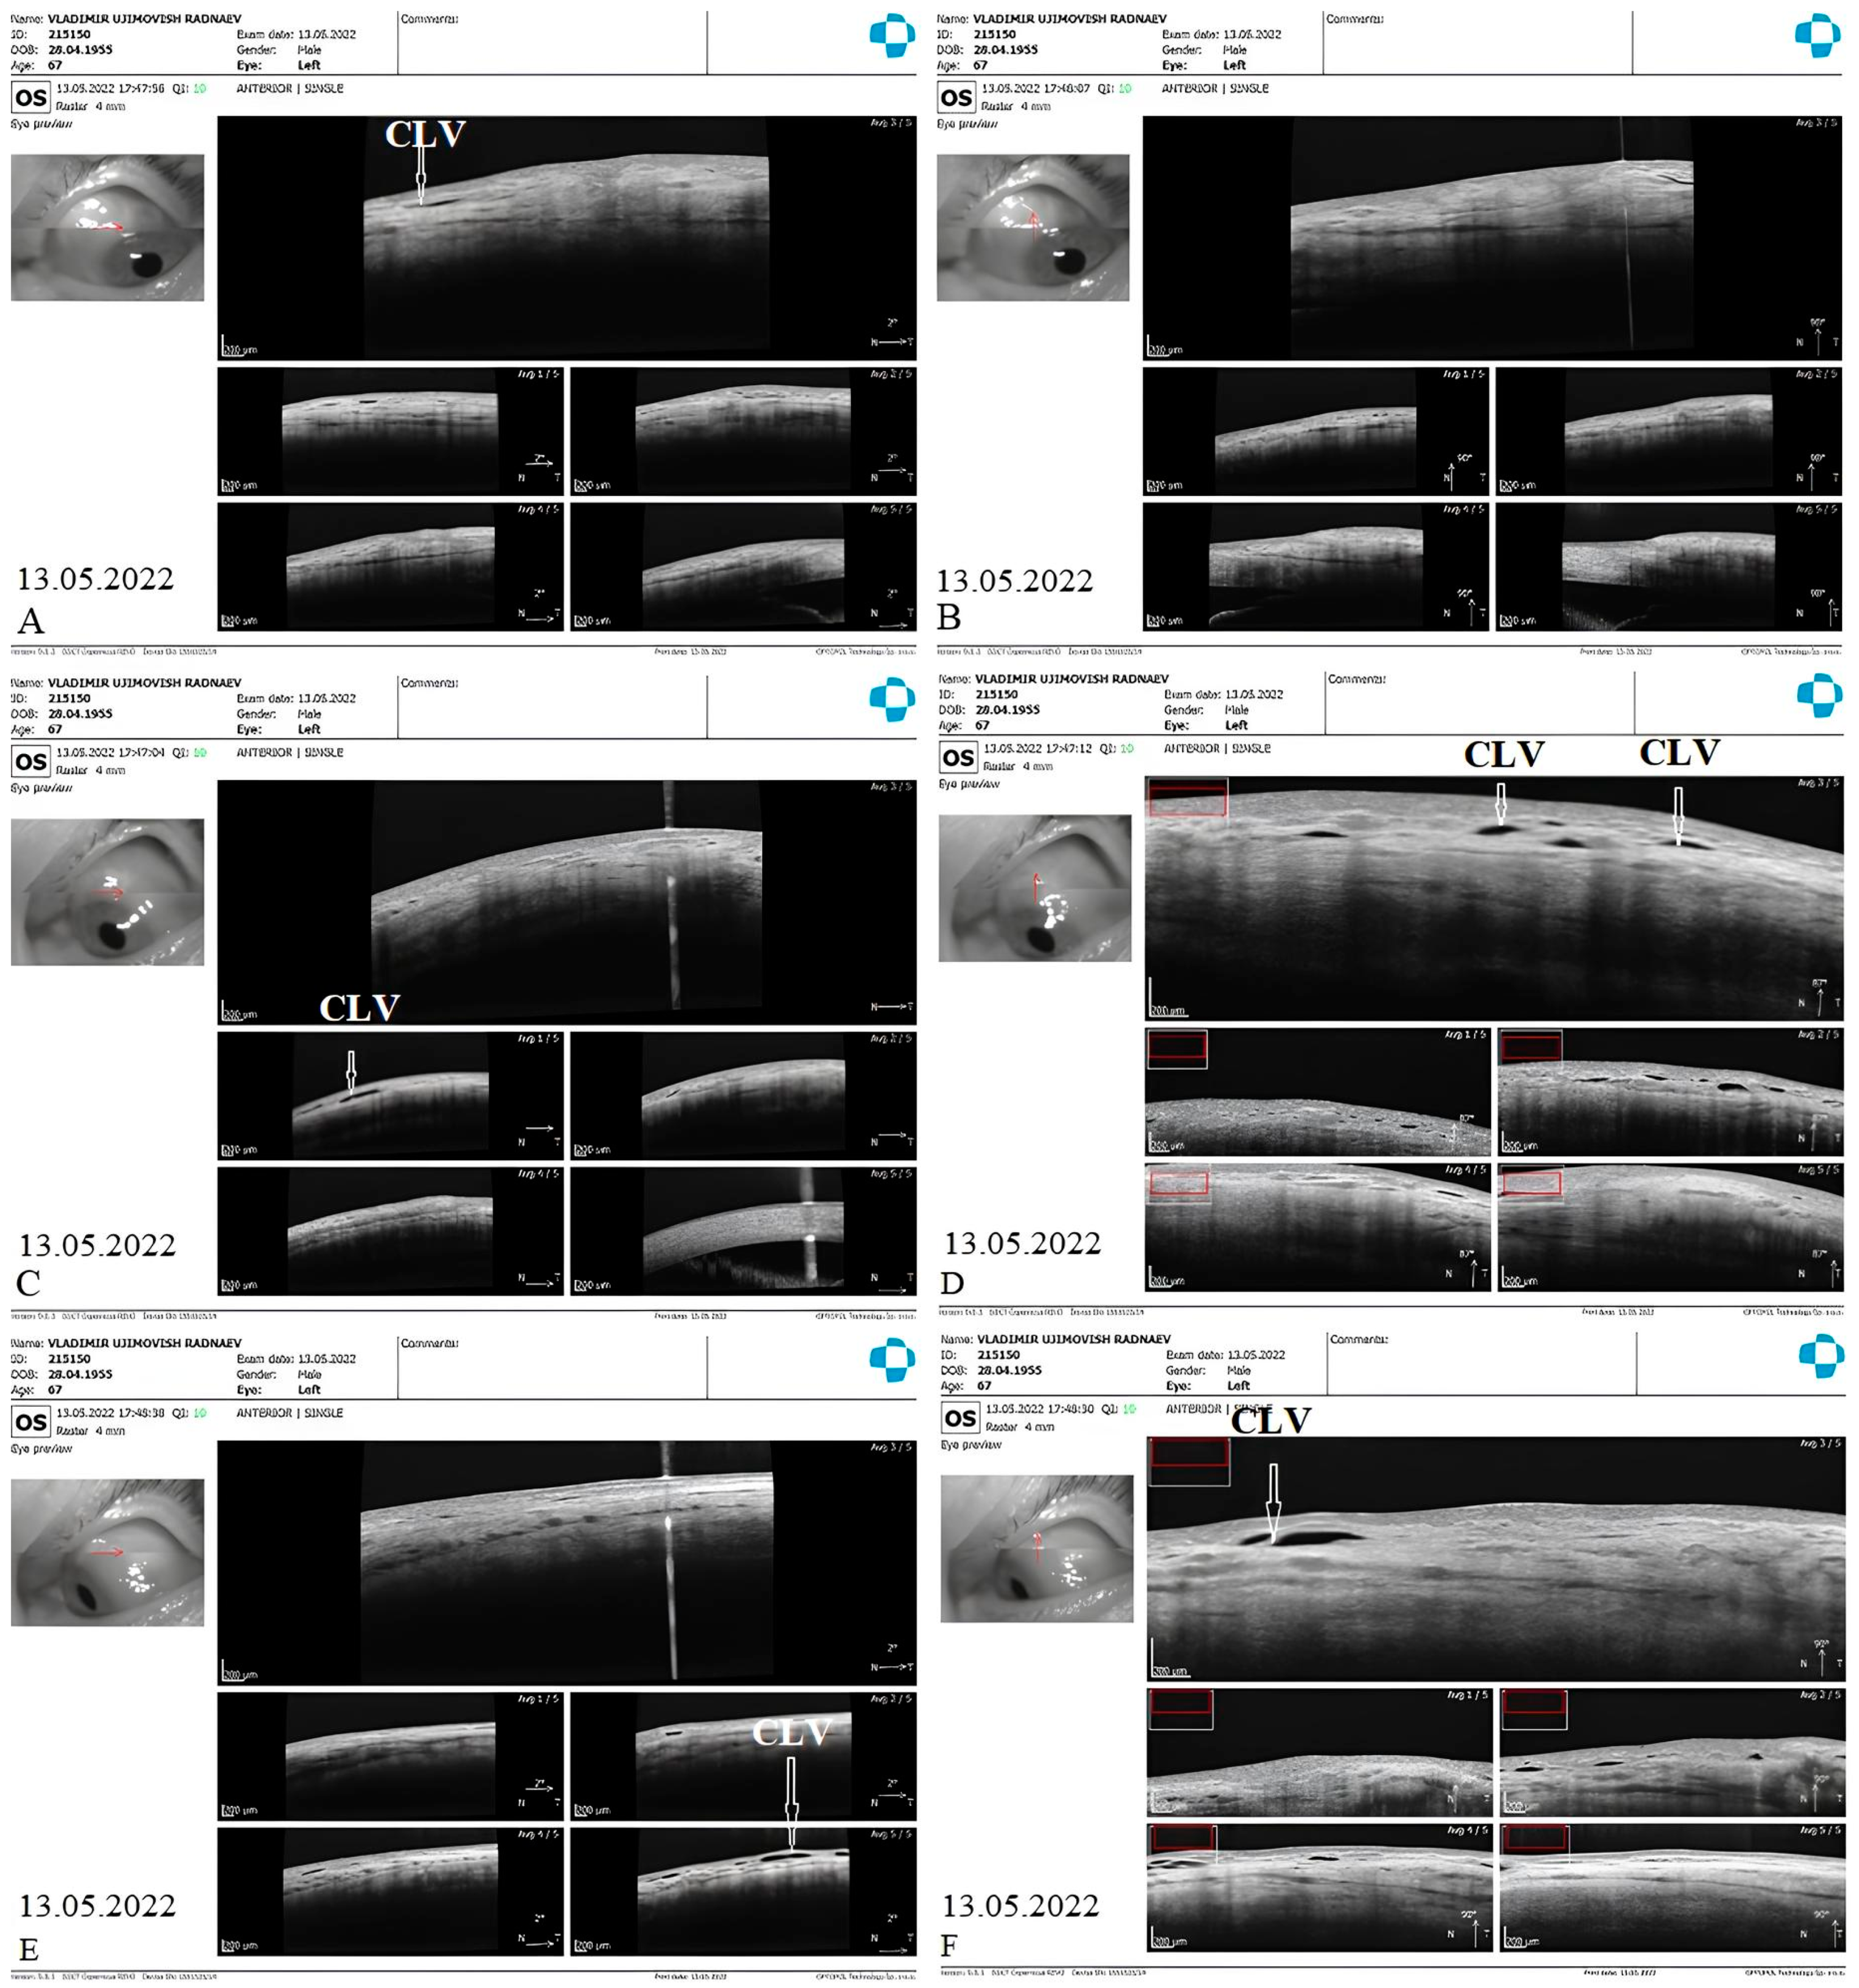

CLV development: At one week after surgery, slit-lamp biomicroscopy revealed an absence of blebs and CLVs. On OCT, the absence of a bleb at the surgical site was confirmed, and CLVs were identified in the superior nasal and temporal quadrants, as well as at the surgical site (Figure 17A–F).

The patient was then consulted after another 2 weeks. On biomicroscopy, CLVs were observed in the superior temporal quadrant (Figure 18A–C); the lymphatics arose directly from the sclera, located at a considerable distance from the surgical site, and became more prominent when the upper eyelid was moved over them (see Supplementary Materials, Video S1_Case 2_month 1 after surgery: CLVs in superior temporal quadrant).

The patient’s subsequent consultation was 1.5 months after surgery. Remnants of CLVs could be identified in the superior temporal quadrant on slit-lamp examination. On OCT, CLVs were identifiable in the superior temporal quadrant and at the surgical site (Figure 19A–D).